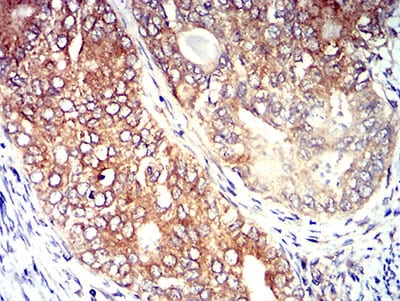

| IHC | 1/200 - 1/1000 | Human,Mouse,Rat |

CD195 antibodies are vital tools for studying CCR5 expression, function, and signaling in diseases like HIV/AIDS, autoimmune disorders, and cancers. They are used in flow cytometry, immunohistochemistry, and functional assays to characterize immune cell subsets or evaluate receptor modulation. Some therapeutic antibodies or small molecules targeting CCR5 aim to block inflammatory pathways in conditions such as rheumatoid arthritis or to inhibit cancer metastasis. Additionally, the CCR5Δ32 mutation, which confers natural resistance to HIV, has spurred gene-editing approaches using CRISPR/Cas9. with CD195 antibodies serving as validation tools.